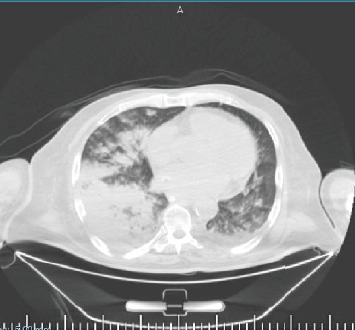

Warfarin is widely prescribed for the prevention of thromboembolic events but carries a well-known risk of bleeding complications. While gastrointestinal and intracranial hemorrhages remain among the more frequent sites, pulmonary hemorrhage is an exceedingly rare case presentation and can be particularly catastrophic. We report the case of a 57-year-old male in Gaza with an extensive medical history of past hospitalization, who presented with severe ecchymosis, with his condition progressing to life-threatening pulmonary hemorrhage. This case occurred amid an active Israeli military assault in November 2024 in the European Gaza Hospital in Khan Yunis, at a time when diagnostic modalities had become limited or completely destroyed and healthcare resources were in severe shortage. The patient was treated with supportive measures, including mechanical ventilation and warfarin reversal using vitamin K and fresh frozen plasma. His anticoagulation regimen was changed to rivaroxaban. This case underlines the difficulties in diagnosing and managing rare but critical hemorrhagic complications in conflict-affected regions and emphasizes the urgency for clinicians to be vigilantly monitoring international normalized ratio values to conduct timely interventions.